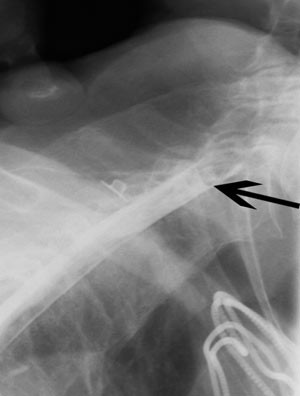

Lumbal spinalpunksjon ga blank spinalvæske med normal dråpetakt og normale verdier for celler, protein og glukose. Pasienten kunne ikke undersøkes med MR grunnet pacemaker. CT av cervikalcolumna viste ingen skjelettskade, men ga heller ingen forklaring på myelopati. Røntgenmyelografi med intratekal kontrast via lumbalt innstikk viste spinalt blokk i nivå C6 (fig 1). Etterfølgende CT avdekket en romoppfyllende prosess bak og til høyre for ryggmargen i samme nivå, som presset ryggmargen mot venstre (fig 2). Ved sagittal (fig 3) og koronal rekonstruksjon så man utstrekningen av prosessen opp til overgangen C2/C3.